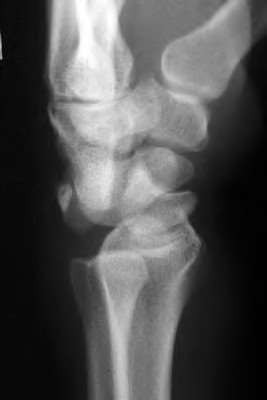

A 22-year-old male falls onto an outstretched hand and sustains a displaced fracture through the proximal pole of the scaphoid. Avascular necrosis of the proximal pole is highly likely due to the disruption of its primary vascular supply. Which vessel provides this critical retrograde perfusion?

Explanation

The primary blood supply to the scaphoid is from the dorsal carpal branch of the radial artery, which enters the dorsal ridge of the scaphoid at the waist and courses proximally. This retrograde blood flow makes proximal pole fractures highly susceptible to avascular necrosis and nonunion. The superficial palmar branch provides a minor supply (about 20%) to the distal pole.